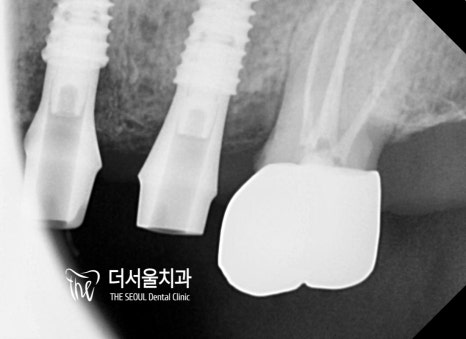

더서울에서는!

기존에 치료 했던 # 25 와 # 24의 크라운을

함께 묶어서 올려드리기로 했습니다.

그 이유는 무엇일까요?

바로 ‘측방압’인데요.

디지털 임플란트 를 심으면 치주 인대가 없기 때문에

옆으로 가해지는 측방압에 약할 수 밖에 없습니다.

만약 너무 과한 힘이 전달이 되면

보철 탈락 및 파절, 수술 실패로 이어질 수 있기 때문에

좀 더 강한 힘에 버틸 수 있도록

두 개의 보철을 하나로 연결하여 제작을 도왔습니다.

교합이나 컨택 등 정확한 위치에 알맞게 들어가 있는 모습이네요.